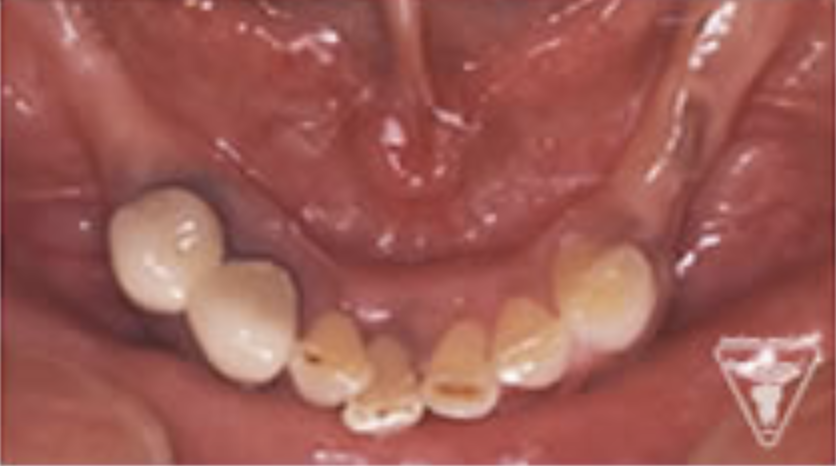

治療前

下の奥歯が左右なくなっており、かみ合わせが深くなっています。

顎のずれは認めませんが、歯肉が厚く中に炎症を取りこみやすいタイプの歯肉です。

左の顎の骨が大きく溶けてなくなっております。